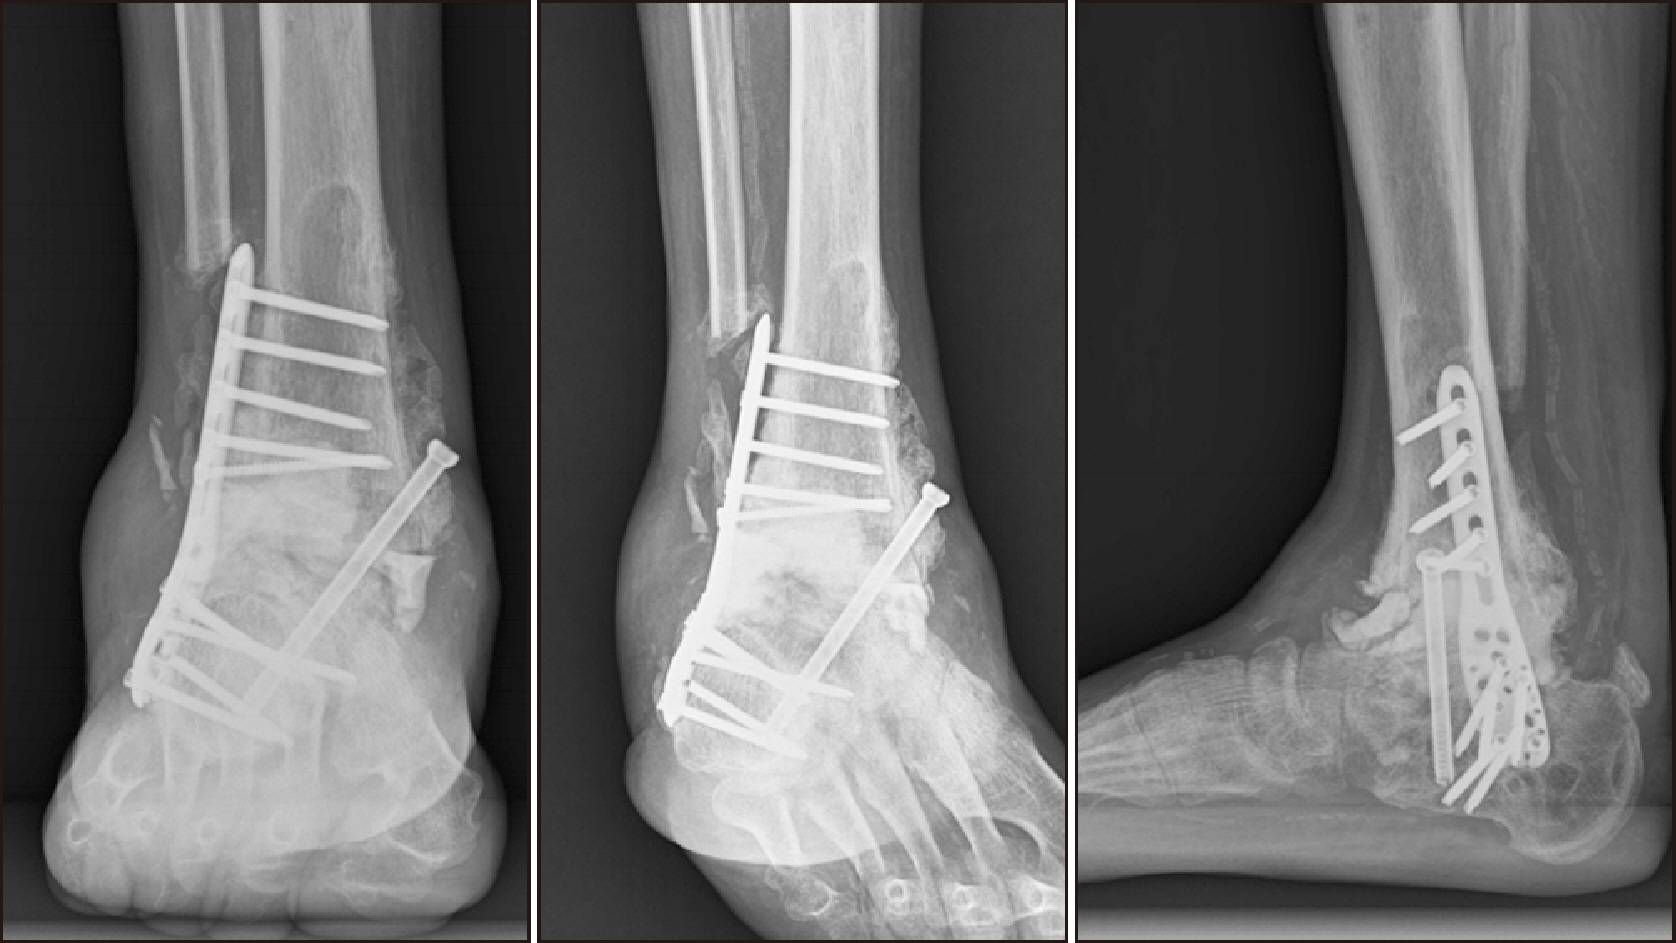

Comprehensive Management of Presumed Underlying Charcot Arthropathy with a Subsequent Traumatic Ankle Fracture in a Patient with Diabetes Mellitus, End-Stage Renal Disease: A Case Report

Charcot neuroarthropathy (CN), also known as Charcot arthropathy, is a complex, progressive disorder primarily affecting the foot and ankle. This case report describes a multifaceted management strategy for a 54-year-old male with diabetes mellitus, end-stage renal disease, and presumed underlying Charcot arthropathy who experienced a traumatic ankle fracture. The initial surgical plans were delayed because of systemic infection indicators, including elevated C-reactive protein levels and high fever. The patient underwent multiple surgical interventions and faced challenges, including metal failure, implant-associated infection, and tibiotalar joint dislocation. A multidisciplinary approach involving orthopedic surgeons, nephrologists, and endocrinologists was crucial for managing the case effectively. In particular, the patient declined a below-knee amputation and opted for comprehensive surgical intervention, resulting in improved functionality at the latest follow-up. This case highlights the complexities of managing CN in patients with multiple comorbidities and emphasizes the need for a nuanced, patient-centered approach.